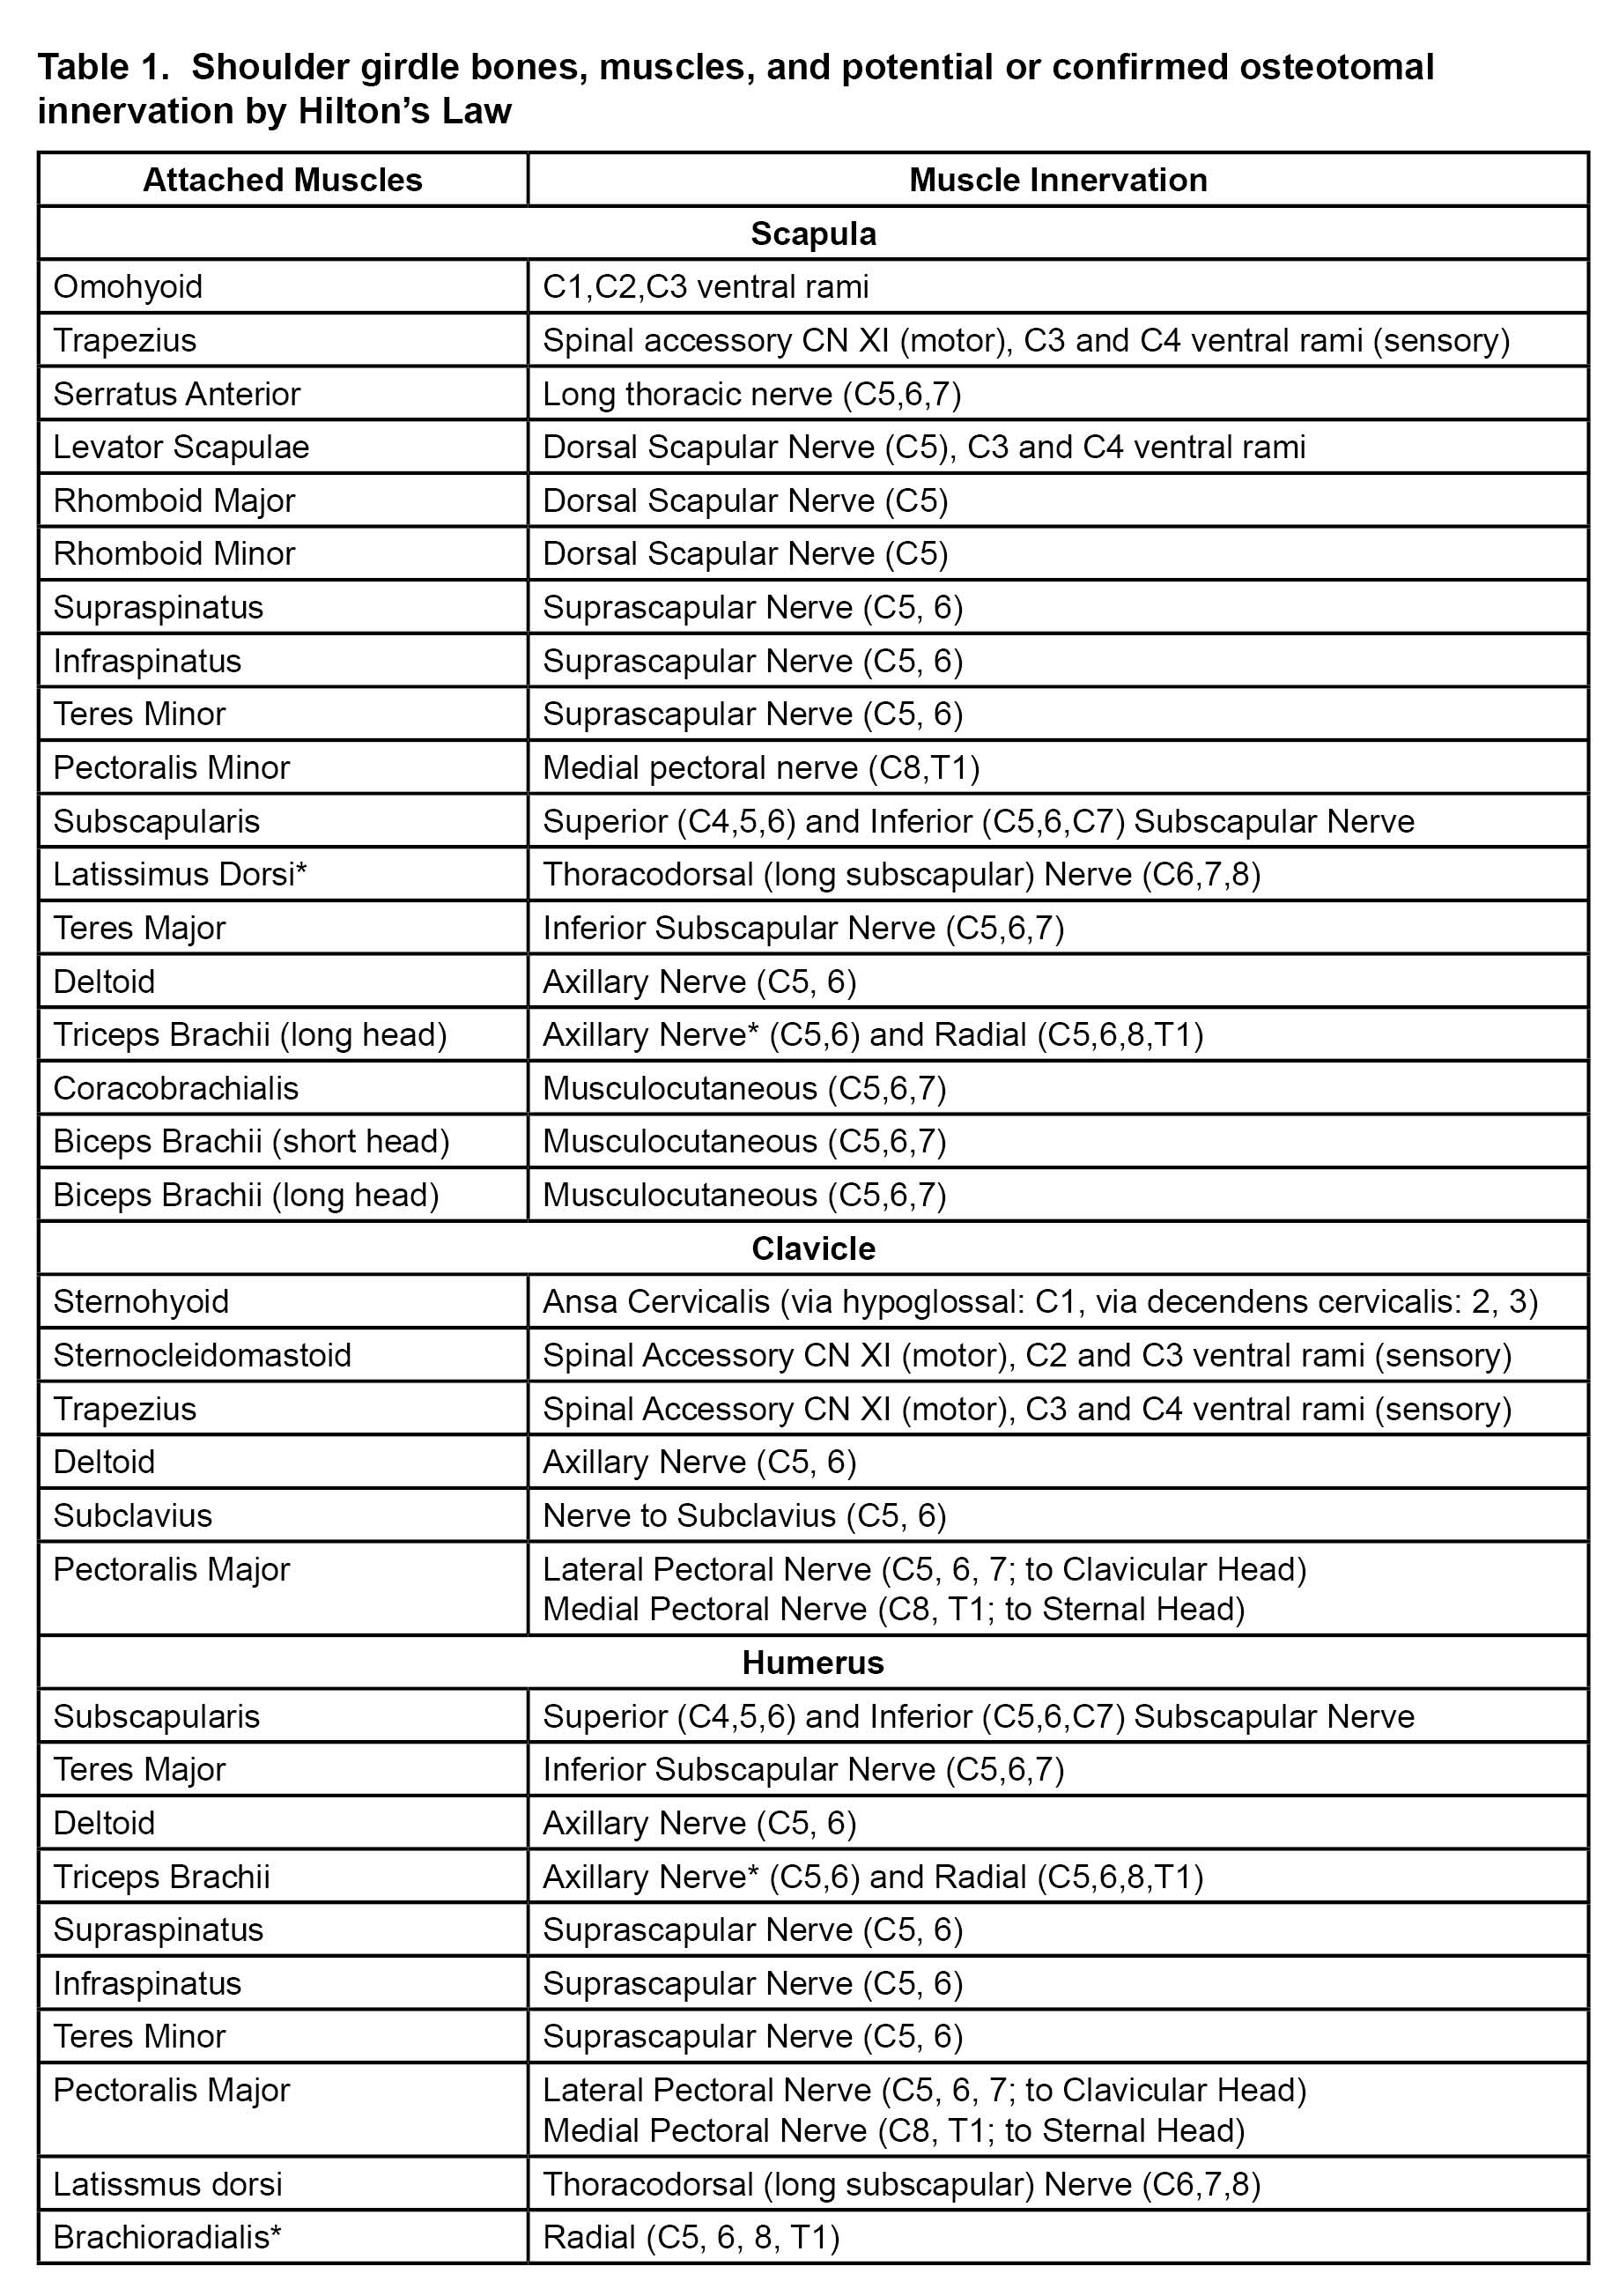

Both thermal and pulsed radiofrequency ablation (RFA) of the suprascapular nerve have been described to treat chronic shoulder pain,[14] but there is a theoretical concern of post-ablation weakness in the supraspinatus and infraspinatus muscles. Eckmann et al, have described the articular innervation of the glenohumeral joint for future techniques in joint denervation via nerve ablation.[25-28] Distal articular sensory denervation can reduce the chance of post-ablation motor weakness. Successful shoulder articular sensory denervation using RFA has been described in the literature.[29],[30] So far, the principal four nerves that innervate the glenohumeral joint and subdeltoid bursa are the suprascapular nerve, axillary nerve, nerve to subscapularis, and, occasionally, the lateral pectoral nerve. Of note, the lateral pectoral nerve provides innervation to the acromioclavicular joint and associated coracoacromial, coracoclavicular, and coracohumeral ligaments. The safe zones for ablation have been defined as the area lateral to the spinoglenoid notch posteriorly (suprascapular branches), at the inferior-posterior portion of the greater tubercle (axillary branches), and over the coracoid process (lateral pectoral branches).[25],[26] These safe zones are depicted in Figure 1. The lateral trunk of the suprascapular nerve also could be ablated (which may spare supraspinatus function but compromise infraspinatus function) midway between the suprascapular notch and spinoglenoid notch in the supraspinous fossa.[28] Nerve to subscapularis should be accessible over the anterior superior neck of the glenoid;[27] however, due to the proximity of this nerve to the brachial plexus and axillary artery, pre-clinical and clinical work on determining ideal ablation trajectory is ongoing by our team. As with the knee and hip joint, shoulder articular ablation is a compromise between full joint denervation and safety. Importantly, the inferior portion of the glenohumeral joint anteriorly and posteriorly is unacceptably close to the motor portion of the axillary nerve and the brachial plexus and too proximate to the circumflex humeral artery to be considered for ablation with perhaps the exception of rare palliative situations.

Herein we describe techniques to block and ablate articular sensory branches of the suprascapular, axillary, lateral pectoral nerves, and nerve to subscapularis using fluoroscopic guidance. We caution that these techniques are emerging and continue to require further pre-clinical and clinical study. We recommend that clinicians study the relevant anatomy closely prior to nerve ablation and disclose potential risks to patients in a fully transparent fashion.